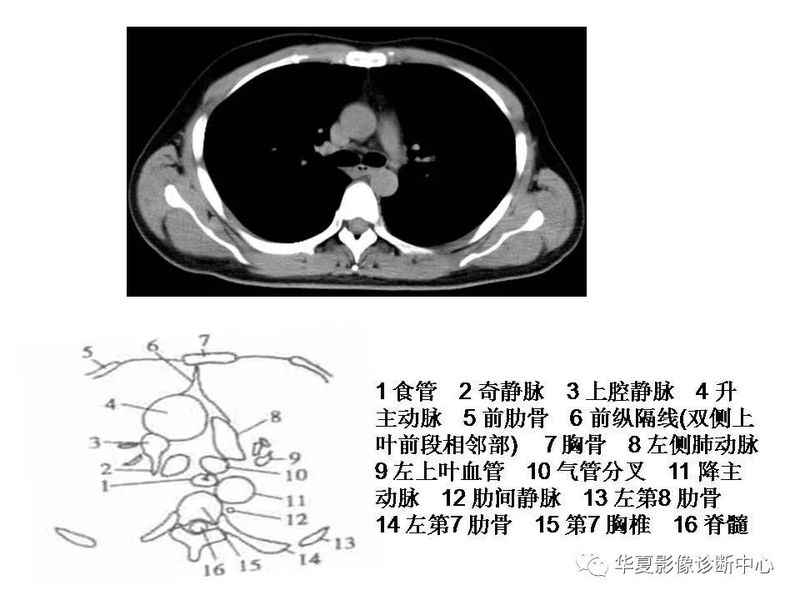

干货 | 汇总胸部CT读片扫盲知识,看懂胸部CT不再难